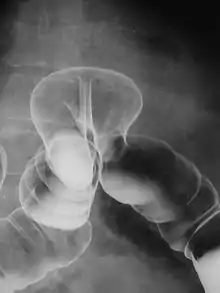

El enema opaco o radiopaco, también llamado colon por enema, es un método de diagnóstico que permite visualizar el interior de la ampolla rectal, sigma, colon descendente, etc. aproximadamente hasta el ángulo de Treitz mediante un enema de un medio de contraste radiopaco (generalmente sulfato de bario, un compuesto químico metálico de color plateado a blanco). A continuación se realiza una radiografía de la zona, en la que, por estar rellena la luz por el contraste, resalta la estructura de la pared interna o revestimiento mucoso del colon.

Cuando se usa bario como medio de contraste combinando con aire para obtener mejores imágenes, se describe como enema con doble contraste. Durante el estudio, se acuesta al paciente sobre la mesa radiográfica y se le coloca el enema con el líquido de contraste.